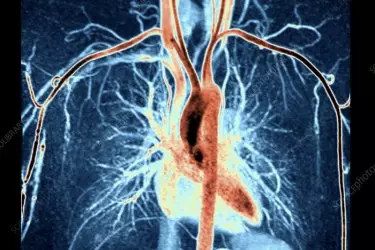

Angiography is the study of blood vessles in the human body. The body has blood vessels in the form of arteries and veins. Apart from the main blood vessles, there are many smaller vessels called secondaries. These blood vessles can have blockages inside them or aneurysms which can be life threatening. The Angiography of the blood vessles can be done either invasively on a Cath Lab or non-invasively on CT Scan or MRI. In angiography study the blood flowing inside the vessels has to be scanned. This becomes possible only with the use of a contrast medium containing iodine as iodine is the only liquid which is radio-opaque. Patients who have deranged kidney function cannot be given this contrast. For such patients there is no other choice but to go for non-contrast MR Angiography. The results of non-contrast MR Angiography have been improving over the years and now match the results of contrast imaging on other modalities like CT Scan.

MR Angiography can be done to visualize the vessels of - Brain, Neck, Heart, Renal, Peripheral, Abdominal and Chest Region.

MR Angiography will detect any aneurysm in the blood vessles or plaques which cause blockages. Arteriovenous Malformation (AVM) or Pulmonary Embolism are also diagnosed on MR Angiography.